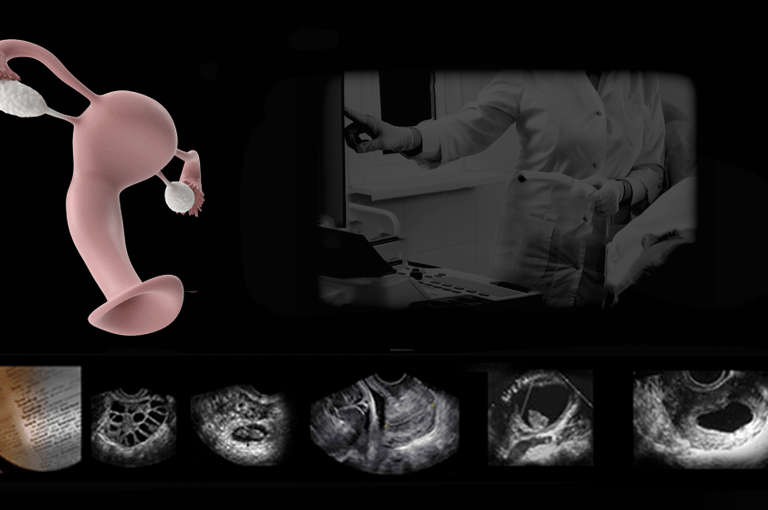

Pelvic imaging brings technical demands and clinical responsibility together. This hands-on course matters because it trains you to approach deep anatomy with precision, interpret subtle cues within context, and make confident calls that directly affect care planning.

We impart a method of precise anatomic dead reckoning to cut your time and seal your confidence. Through guided scanning and focused repetition, you’ll develop the skill and judgment to move beyond uncertainty to actionable insight.

Taught as spatial navigation, not pattern memorization – Develop true 3D anatomic understanding from 2D images, eliminating probe-guessing and hesitation.

Hands-on dominance from the first moment – Guided, deliberate scanning forms the foundation of learning rather than extended lecture or observation.